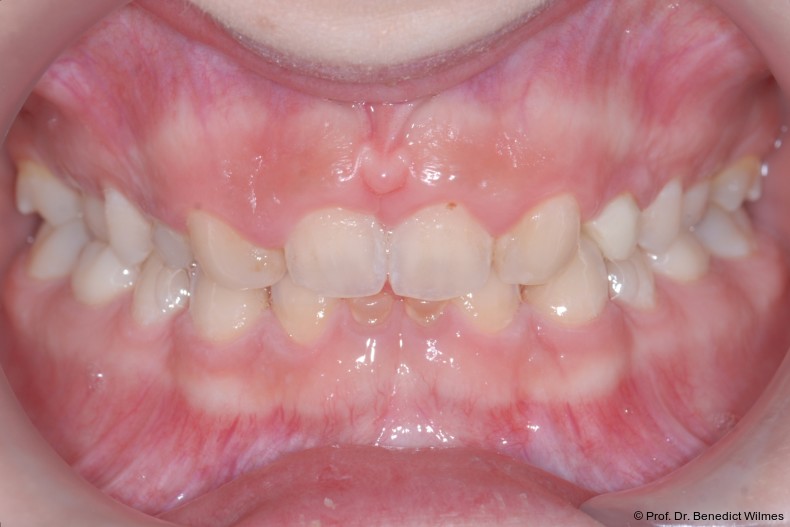

Ein 14-jähriger Patient wurde bei Aplasie der beiden oberen seitlichen Schneidezähne mit dem Ziel der beidseitigen Lückenöffnung kieferorthopädisch therapiert (Abb. 1a+b). Zum Ende der kieferorthopädischen Behandlung wurden zwei Miniimplantate in Regio 2er als temporärer Zahnersatz inseriert (Benefit System, PSM, 2 x 13 mm, Abb. 2a+b). Nach Abdrucknahme wurden Kronen auf den Peek-Abutments modelliert und diese mit Kunststoff auf die Abutments geklebt (Abb. 3a–d). In den Abbildungen 3 und 4 sind die klinischen und röntgenologischen Nachkontrollen innerhalb der nächsten achteinhalb Jahre dokumentiert. Man erkennt einen sowohl in der Höhe als auch in bukkopalatinalen Breite verbleibenden gesunden Knochen ohne Anzeichen einer Atrophie. Im Alter von 23 Jahren wurden die definitiven Implantate ohne die Notwendigkeit einer Augmentation eingesetzt (Abb. 5) und nach Einheilung prothetisch versorgt (Abb. 6a–e und Abb. 7a–c).

Bei einer elfjährigen Patientin fehlten bei Zustand nach Frontzahntrauma im Alter von neun Jahren beide oberen mittleren Schneidezähne (Abb. 8a+b). Als temporärer Ersatz wurden Miniimplantate (Abb. 9, 2 x 13 mm) eingesetzt und Kronen im Labor angefertigt, welche auf den Miniimplantaten verschraubt wurden (Abb. 10a+b). Die Miniimplantate wurden im Alter von 19 Jahren, also nach achtjähriger Nutzung (Abb. 11a+b), durch dentale Implantate ersetzt.

Bei einer 13-jährigen Patientin lag eine Aplasie multipler Zähne, unter anderem auch der oberen seitlichen Seitenzähne vor. Die Eckzähne brachen bei dieser Patientin direkt neben den mittleren Schneidezähnen durch (Abb. 12).